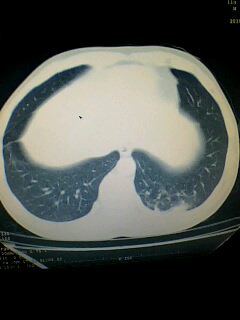

标题: CT28315:咳嗽咳痰咯血半月并胸痛 [打印本页]

标题: CT28315:咳嗽咳痰咯血半月并胸痛

图像资料欠清,建议强化,考虑周围型肺癌。

左下肺肿块影,深分叶,考虑肺癌。

左下肺球形病灶,考虑:1:球形肺炎;2:周围型肺癌不除外,建议治疗后复查

考虑左肺下叶周围型肺癌.